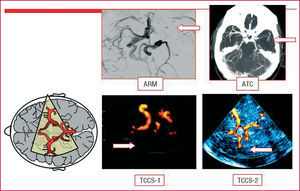

Se realizará un estudio dúplex/Doppler de troncos supraaórticos (DTSA) y transcraneal (DTC) en todos los pacientes que han experimentado un ictus isquémico. El estudio carotídeo nos permitirá diagnosticar la etiología aterotrombótica del ictus isquémico y valorar tratamientos preventivos específicos como la endarterectomía carotídea. El Doppler/dúplex transcraneal nos permite diagnosticar estenosis intracraneales, valorar la circulación colateral, confirmar la recanalización arterial después de administrar un tratamiento fibrinolítico (fig. 2) e incluso detectar una comunicación derecha-izquierda (shunt) por un foramen oval permeable (FOP) mediante el test de microburbujas. Por otro lado, aporta un información valiosa en la evaluación preoperatoria y pronóstica de la estenosis carotídea (estudio de circulación colateral, estudios de reserva hemodinámica y detección de microembolias) (tabla 2). Un error frecuente es limitar el estudio ultrasonográfico en pacientes con estenosis carotídea al análisis de las arterias cervicales.

Fig. 2. Oclusión intracraneal de la arteria cerebral media. Imagen obtenida mediante angiorresonancia magnética craneal (ARM), angiotomografía computarizada craneal (ATC) y dúplex transcraneal (TCCS 1-2).

La elevada sensibilidad y especificidad del estudio ultrasonográfico (dúplex color de troncos supraaórticos más Doppler/dúplex transcraneal) permite plantear, asociada a alguna otra técnica de imagen no invasiva como la angio-RM o la angio-TC, la posibilidad de indicar la endarterectomía sin la utilización de la angiografía por sustracción digital.